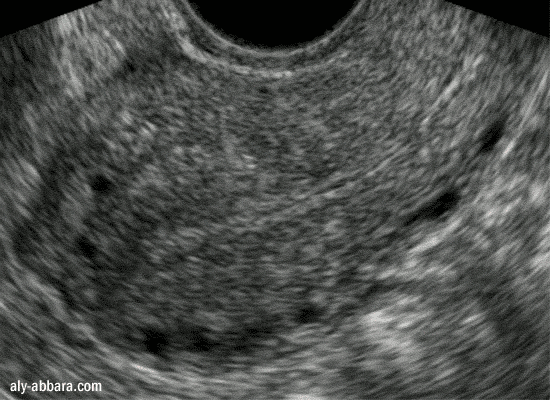

Hypotrophie de l'endomètre chez une patiente sous

contraception par progestatif normodosé et se plaignant de métrorragie

Endomètre de 2,5 mm d'épaisseur au 12ème jour du cycle menstruel